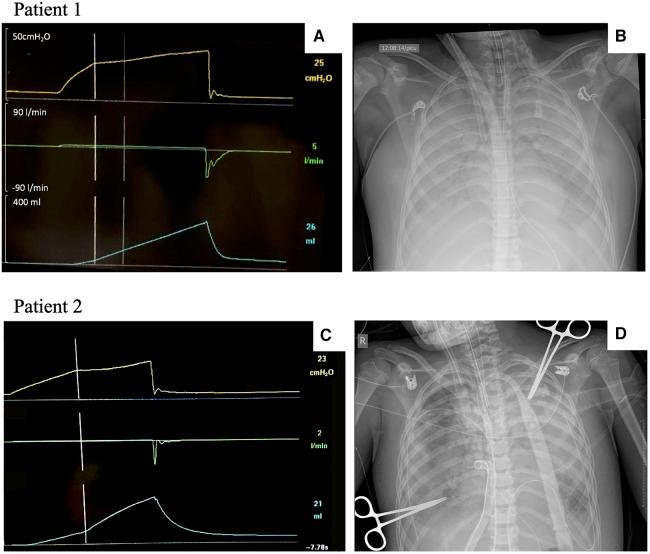

Airway closure was simulated, and AOP was visible at 15 cmHO with a clear inflection point, except for the 3 kg simulated patient. Regarding insufflation time, a 4 s maneuver exhibited a better performance in 30 and 50 kg simulated patients since shorter insufflation times had excessive flowrates (>10 L/min). Below 20 kg, the difference in resistive pressure between a 3 s and a 4 sec maneuver was negligible; therefore, prolonging the maneuver beyond 3 s was not useful. Airway closure was identified in two p-ARDS patients, with the pediatric maneuver being employed in the 28 kg patient.

We propose a pediatric AOP maneuver delivering 6 ml/kg of Vt at a continuous low-flow inflation for 3 s for patients weighing up to 20 kg and for 4 s for patients weighing beyond 20 kg.